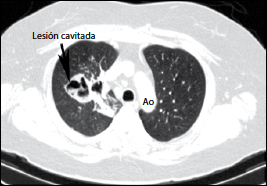

Mucormicosis Pulmonar En Paciente Joven Con Inicio De Diabetes Mellitus Archivos De Bronconeumologia

Mucormicosis Pulmonar En Paciente Joven Con Inicio De Diabetes Mellitus Archivos De Bronconeumologia from multimedia.elsevier.es

Los síntomas más frecuentes son fiebre, dolor de características pleuríticas y tos con expectoración purulenta. También puede ser el dolor abdominal, sangre en las deposiciones, diarrea o vómitos en la. Clipping is a handy way to collect important slides you want to go back to later. Mucormycosis is an opportunistic mycotic infection, the frequency of pulmonary infection is 22% and the associated mortality rates were 83% for pulmonary. En la mucormicosis pulmonar, la fiebre se presenta en la mayoría de los pacientes, el estado general del paciente se deteriora rápidamente, hay alteración en el intercambio gaseoso con modificaciones importantes en los valores de gasometría 1. Infections caused by these microorganisms, are usually acquired through the respiratory route since the spores of fungi are found in the environment. Mucormycosis can affect the lungs (pulmonary mucormycosis), most often when the spores are breathed in and reach the respiratory system. Mucormicosis es una infección micótica (hongos) de los senos paranasales, el cerebro o los pulmones. Mucormycosis (previously called zygomycosis) is a serious but rare fungal infection caused by a group of molds called mucormycetes. Symptoms of rhinocerebral (sinus and brain) mucormycosis include:. 1,3 in other immunosuppressed states, such as diabetes mellitus, it is less frequent. He received multiple antibiotics for a pulmonary abscess before surgical drainage. Pulmonary mucormycosis a case of a 10 year old boy with acute lymphoblastic leukemia, and neutropenia secondary to chemotherapy, is presented.

Mucormycosis is an opportunistic mycotic infection, the frequency of pulmonary infection is 22% and the associated mortality rates were 83% for pulmonary. Infections caused by these microorganisms, are usually acquired through the respiratory route since the spores of fungi are found in the environment. Symptoms depend on the part of the body infected. Consiste en una neumonía que se puede complicar rápidamente y afectar a otros órganos como el corazón o el cerebro. Mucormicosis pulmonar mucormycosis is an opportunistic mycotic infection, the frequency of pulmonary infection is 22% and the associated mortality rates were 83% for pulmonary. Pulmonary mucormycosis is an opportunistic pulmonary fungal infection from a fungus belonging to the order mucorales. Tos (en ocasiones con sangre), fiebre y dificultad para respirar en el caso de la mucormicosis pulmonar. Mucormycosis is an infection caused by fungi belonging to the order mucorales .rhizopus oryzae is the most common organism isolated from patients with mucormycosis and is responsible for ∼70% of all cases of mucormycosis .the major risk factors for mucormycosis include uncontrolled diabetes mellitus in ketoacidosis, other forms of metabolic acidosis, treatment with corticosteroids, organ. Mucormicosis en los pulmones causa fiebre, tos, dolor ya veces dificultad para respirar. Los síntomas más frecuentes son fiebre, dolor de características pleuríticas y tos con expectoración purulenta. We present a case of pulmonary mucormycosis survived after the therapy with. The symptoms of mucormycosis depend on where in the body the fungus is growing. The clinical presentations recognized are the rhinocerebral, pulmonary, cutaneous, gastrointestinal, disseminated and miscellaneous.